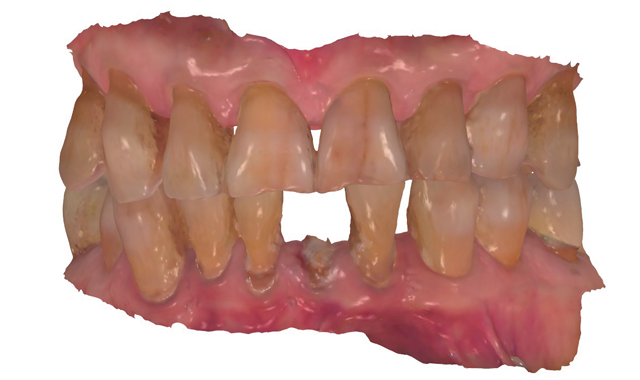

An 88-year-old man presented for restoration of tooth #25, which was fractured and had been endodontically treated (Fig. 1). A thorough intraoral and radiographic examination was performed, which revealed damage to the remaining anterior mandibular teeth incurred over the years as a result of scaling and curettage (Fig. 2). This damage to the

root surface of the lower incisors-which was visible on the radiograph (Fig. 3)-is known as “Riffle-ization.” Described by Dr. Riffle as a technique for removing every last bit of calculus during repeated root scaling, what is now known as “Riffle-izing," ultimately-over the years-changes the shape of the neck of the tooth to resemble an hour glass.

Therefore, based on the clinical and visual evaluation, the preferred treatment would be to restore the fractured #25 with a post and crown and four splinted crowns to restore the anatomy of the four incisors and increase their resistance to both mobility and fracture.